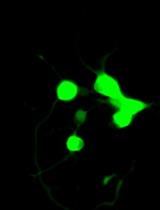

Dynamic light scattering analysis showed that the average sizes for blank nLNPs (Figure 3) and IL-22/nLNPs (Figure 5) are 189.9 ± 69.3 and 184.2 ± 84.96 nm, respectively, based on triplicate measurement.

Figure 3. Measurement of size in blank nLNPs. Particle size was determined to be 189.9 ± 69.3 nm in diameter.